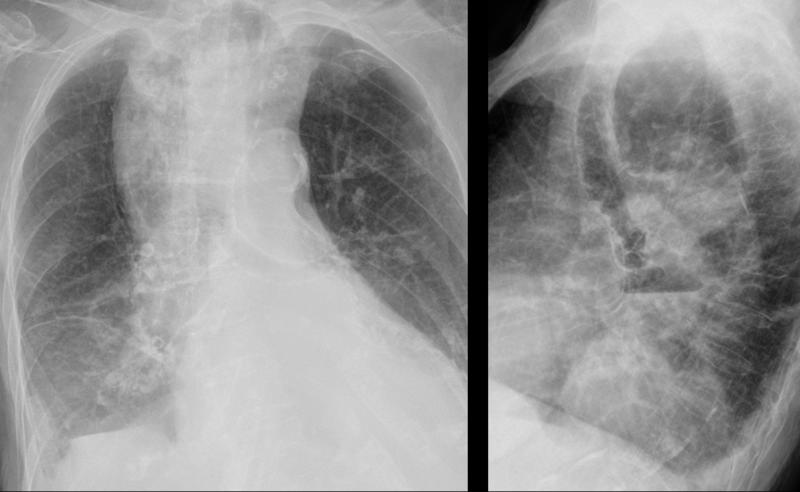

Dilated esophagus- Pa and lat from different dates